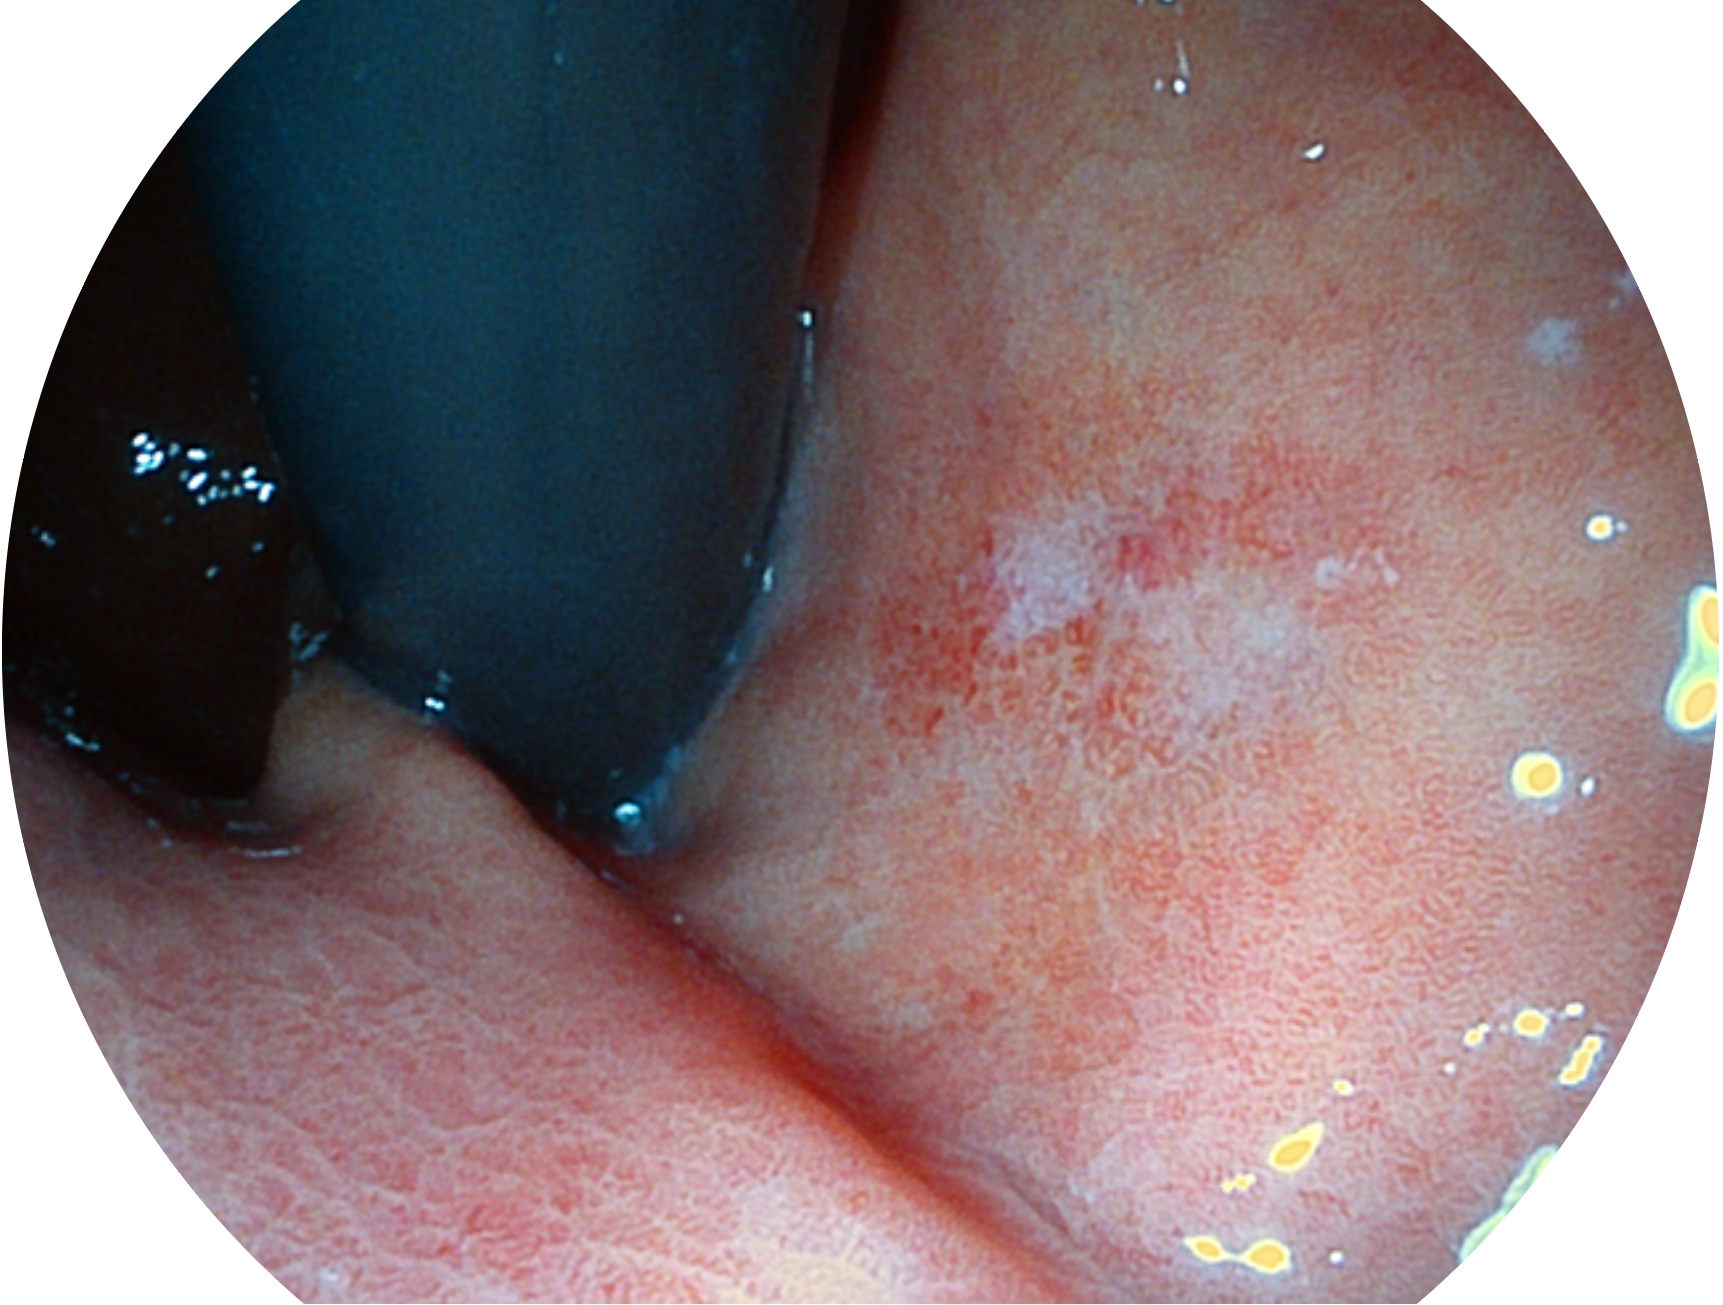

• 白光图像 VIST图像